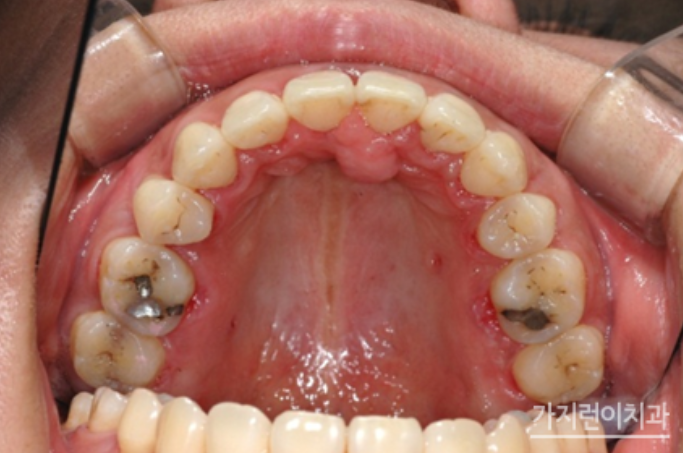

위 사진처럼 설측으로는 복잡해보이는 장치가 보이지만 이를 앙 다문 상태에서는 장치가 보이지 않는데요. 두 개의 와이어를 사용해 치아이동에 필요한 힘을 효과적으로 줄 수 있는데다 치아의 쓰러짐을 방지해 마찰력을 줄여 결과적으로는 치료기간이 크게 단축되었다는 것을 볼 수 있습니다. 게다가 덧니, 돌출입, 비발치 교정 등 기존 설측교정장치보다 빠르고 탁월한 결과를 얻어볼 수 있겠습니다.

엑스레이 사진을 통해 확인할 수 있는 안모 변화도 눈에 띄는데요. 24개월이 소요된 교정기간 동안 장치는 티 나지 않으면서 교정을 완성할 수 있었기에 환자분의 만족도도 높은 편이었습니다. 탄댐설측교정 후에는 자연스럽게 입을 다물 수 있어 자연스레 미소를 머금던 모습이 기억나는데요. 티 나지 않는 직장인 교정으로 속 앓이 없이 성공적인 교정을 해보고 싶다면 본원을 방문해 탄댐설측교정 상담을 받아보시기 바랍니다.